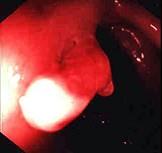

问题 男性,40岁,15年前出现解黏液血便,当时诊断为溃疡性结肠炎,一直服药治疗,病情反复,今大便正常已2年。查体浅表淋巴结无肿大,腹软,无压痛,未及包块,肠鸣音正常。肠镜检查图片如下,最可能是 ( )

选项 A.溃疡性结肠炎中的炎性息肉 B.结肠癌 C.Crohn病 D.肠结核 E.结肠腺瘤

答案 A